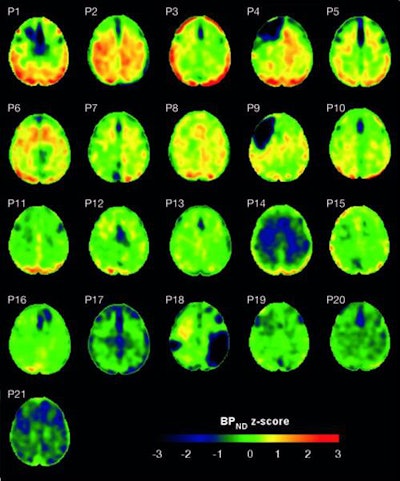

To answer the question, the researchers looked at 21 patients (median age, 49 years; range, 29-72 years) with one moderate-to-severe TBI. Examinations of their injuries, primarily from traffic accidents (86%), occurred at a median age of 32 years (range, 18-51 years). For comparison purposes, 11 age- and demographically matched healthy controls were included in the study.

Flortaucipir-PET images showed significantly greater tracer binding to tau deposits in the right lateral occipital cortex (p < 0.05) of TBI patients, compared with the healthy controls. In addition, white-matter integrity, as measured by fractional anisotropy, was significantly reduced in TBI patients (p = 0.04), compared with healthy controls.